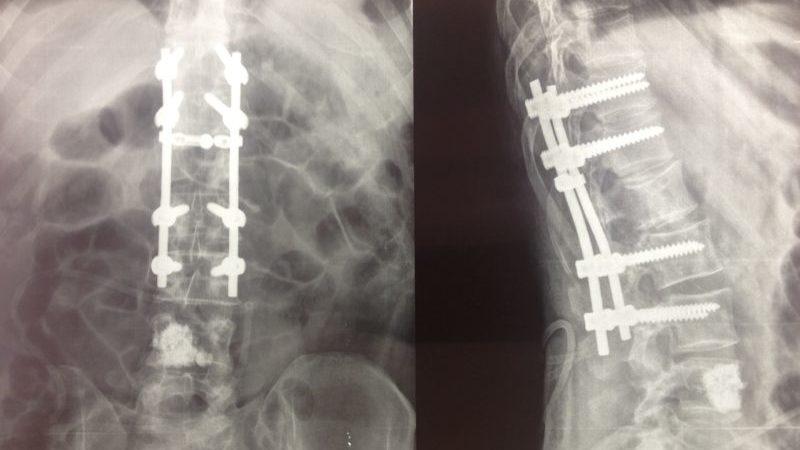

Стабилизация позвоночника осуществляется с использованием металлических конструкций, таких как специальные пластины и болты. Установка имплантов применяется при различных травмах позвоночника, однако чаще всего операции выполняются при дегенеративных заболеваниях, сопровождающихся сильными болями и риском развития паралича. После операции период восстановления, как правило, минимален.

Для подобных операций используются металлические конструкции различных размеров и форм:

- При установке конструкций внутри костного канала применяются сплошные или полые стержни, интрамедуллярные стержни с блокировкой и без нее.

- При установке конструкций на кость используются скобы, винты и пластины.

Хирургическое лечение травмы позвоночника с применением титановых металлоконструкций отечественной разработки. Для заднего спондилодеза применяется транспедикулярный фиксатор. Для переднего спондилодеза применяются имплантаты: сетчатые имплантаты для замещения тел позвонков, пластины с винтами.